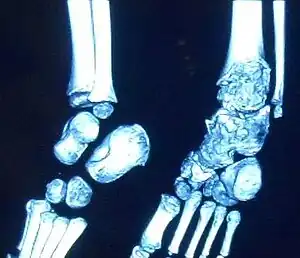

| Trevor disease in a nine-year-old girl: talus | |

This disorder is rare, and is characterised by an asymmetrical limb deformity due to localized overgrowth of cartilage, histologically resembling osteochondroma. It is believed to affect the limb bud in early fetal life. The condition occurs mostly in the ankle or knee region and it is always confined to a single limb. This usually involves only the lower extremities and on medial side of the epiphysis. It is named after researcher David Trevor.[1]

Trevor disease was first described by the French surgeon Albert Mouchet and J. Belot in 1926. In 1956, the name "dysplasia epiphysealis hemimelica" was proposed by Fairbank.[1] The usual symptoms are the appearance of an osseous protuberance, on one side of the knee, ankle or foot joint which gradually increases Radiologically,[14] the condition shows a nonuniformity of growth and multiple unconnected ossification centers around the epiphyses.[8]